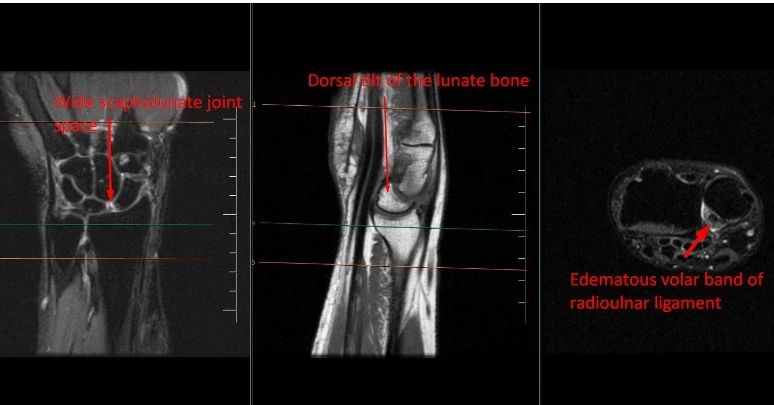

*Scapholunate Joint Instability: marked widening of the scapholunate joint space with scapholunate ligament tear at the dorsal band*.

• Dorsal tilt of the lunate bone suggestive of dorsal intercalated segmental instability (DISI)

• Focal tear of volar band of distal radioulnar ligament with widening of the posterior radioulnar joint space with small effusion.